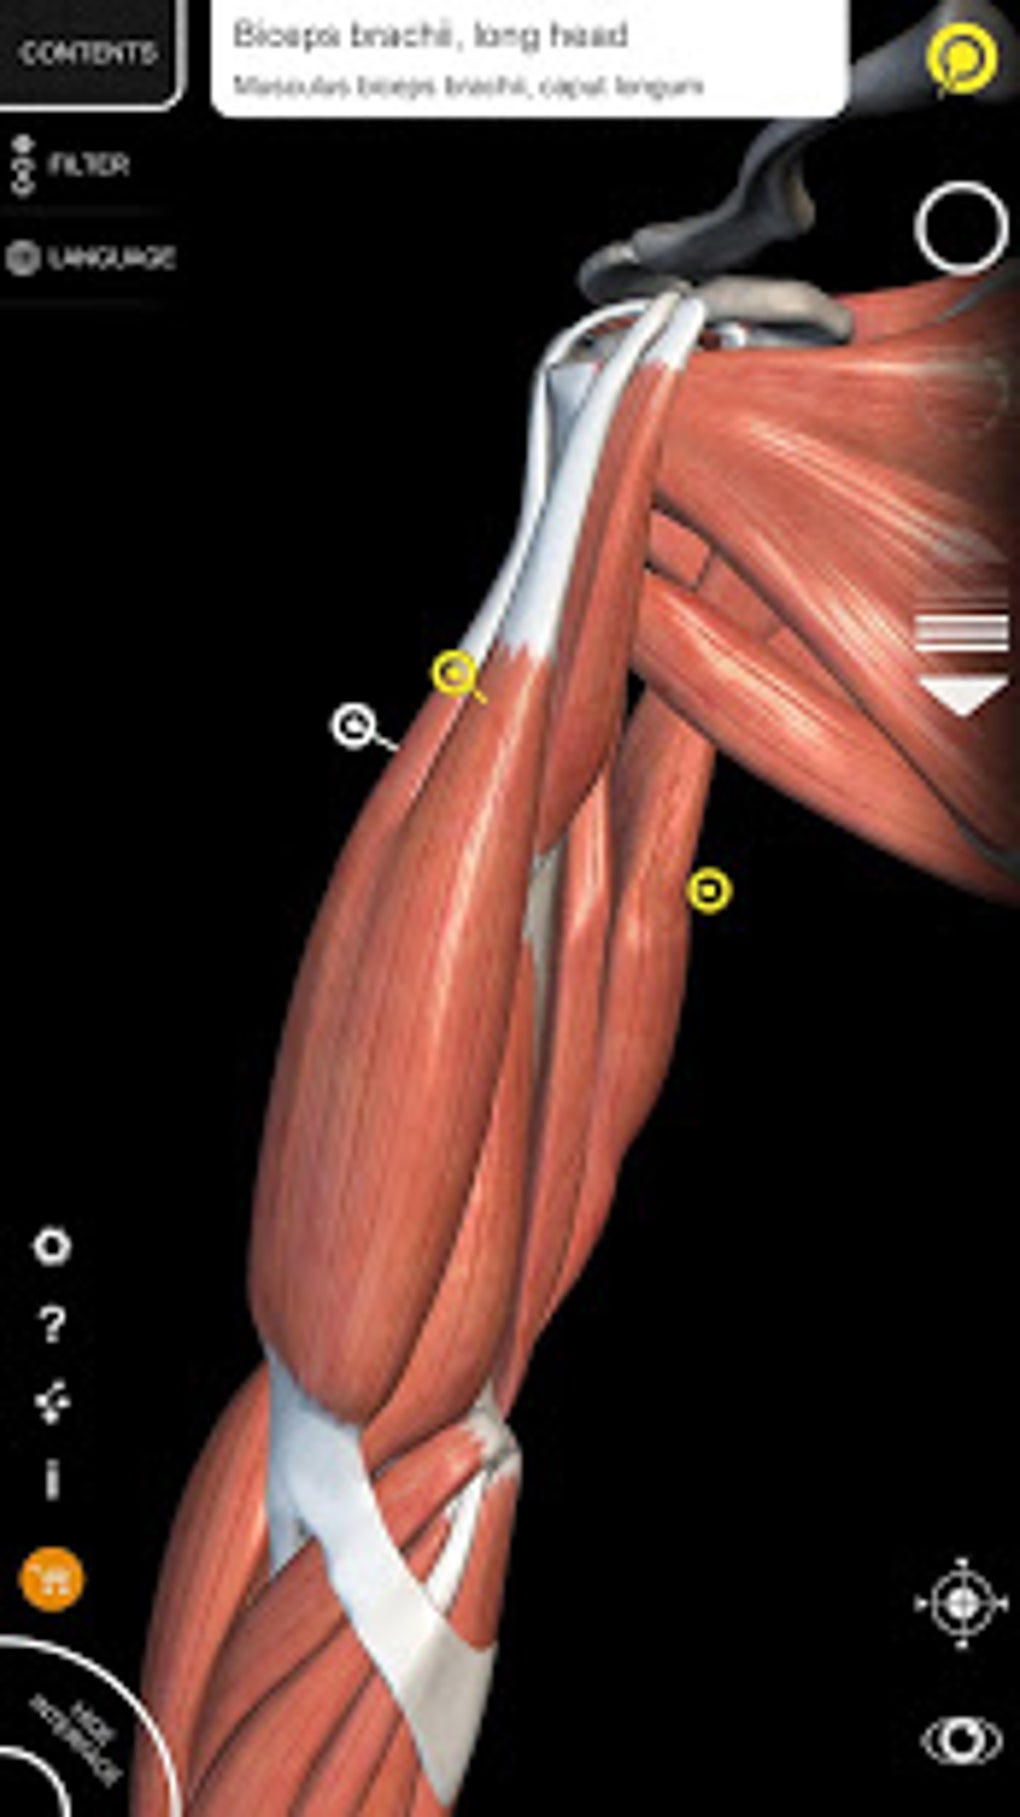

The app is based on the 3D model of the human body which is built with skeleton, muscles, bones, organs, and tissues. The anatomical models you will see in this app are the Respiratory System, Lymphatic system, Digestive System, Cardiovascular system, Eye and ear, and more.This app allows you to view the anatomy from a variety of angles, which makes it easy to study and understand.